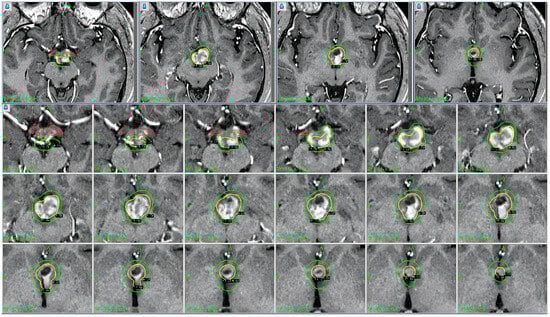

Figure 2. The patient underwent placement of the Leksell stereotactic head frame without difficulty. This was followed by obtaining a high-resolution stereotactic MRI scan of the brain. Contrast-enhanced T1-weighted axial images were obtained at 2 mm intervals. The images were transferred into the treatment planning workstation and reviewed. The previously identified enhanced lesions involving the hypothalamus were observed. Operative procedure: the team proceeded with outlining the visible lesion and developing a treatment plan. A single dose calculation matrix was used. The hypothalamic lesion was treated using 9 shots with 4 and 8 mm collimator helmets. The volume target was 2.6 cm3, and the prescription isodose was 11 Gy. White to the 50% isodose line. Note: 100% of the tumor received the prescription isodose. Brain stem < 11 Gy, left optic nerve < 7.8 Gy, and right optic nerve < 5.1 Gy.

GKRS was performed using advanced stereotactic navigation, which enabled precise delineation of the tumor margins while minimizing radiation exposure to the surrounding healthy tissues (Table 2). The radiosurgical plan was carefully developed to provide optimal dose coverage to the lesion while adhering to dose constraints for critical structures, particularly the optic chiasm, brainstem, and hypothalamus. A marginal dose of 14 Gy was delivered to the 50% isodose line, which provided an effective tumoricidal dose with minimal risk of radiation-induced complications. The precision afforded by stereotactic targeting was integral to achieving the therapeutic objectives, given the high sensitivity of the surrounding anatomy to radiation.

Description: The table provides a summary of the data collected during a stereotactic radiosurgery session to treat a glioma. A maximum dose of 22.0 Gy was delivered to the tumor target, with a total of 9 radiation shots administered. The prescribed dose was 11.0 Gy, which was delivered to the 50% isodose line. To guarantee high accuracy in dose delivery, stereotactic coordinates (X = 96.5 mm, Y = 108.5 mm, and Z = 107.0 mm) were employed to achieve precise localization with a spatial resolution of 1.0 mm. The treatment was carefully planned to optimize tumor control while minimizing radiation exposure to adjacent healthy structures, as evidenced by the total beam-on time of 109.6 min.

Table 2: This table details “Run 1 (90 degrees)” in a stereotactic radiation session, with six shots targeting specific coordinates (X: 94.7–103.9 mm, Y: 101.2–114.6 mm, Z: 101.3–112.1 mm). Collimator settings mainly used position 8, with selective use of position B. Shot durations ranged from 8.89 to 14.12 min, reflecting precise, tailored dose delivery to the target area.

Table 3: This table provides a detailed description of “Run 2 (110 degrees)” in a stereotactic radiation session, which involves three shots aimed at precise coordinates in the X, Y, and Z planes. The collimator settings predominantly utilize position 8, with occasional utilization of position B. The shot durations vary between 12.25 and 14.85 min, demonstrating accurate and tailored administration of the dosage to the specific target areas.